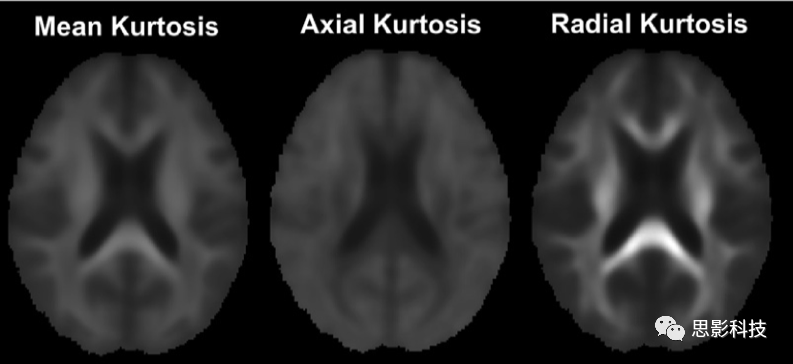

1)彌散峰度成像(diffusion kurtosis imagingDKI)

擴散峰態(tài)成像(DKI)是一種表征非高斯擴散的成像方法,即通過估計位移分布的過度峰態(tài)來表征非高斯擴散,計算出平均峰度(MK)、軸向峰度(AK)、徑向峰度(RK)等標量指標進行進一步基于體素的統計分析。

圖例 DKI指標